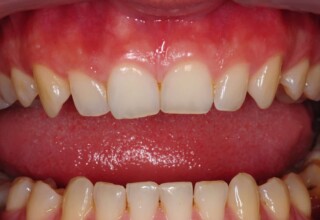

Composite Resin Veneers

Resin veneers are an inexpensive mode of esthetic improvement of anterior teeth, premolars also. Their potential is admirable and their limit is the operator’s clinical dexterity and imagination. In this case there were multiple problems with the upper four incisors: staining, poor inclinations, diastemas, multishading, poor interrelationship and poor tooth-gingiva ratios. They were restored with four direct composite resin veneers (one on a porcelain implant crown!) which were manufactured intraorally!!!